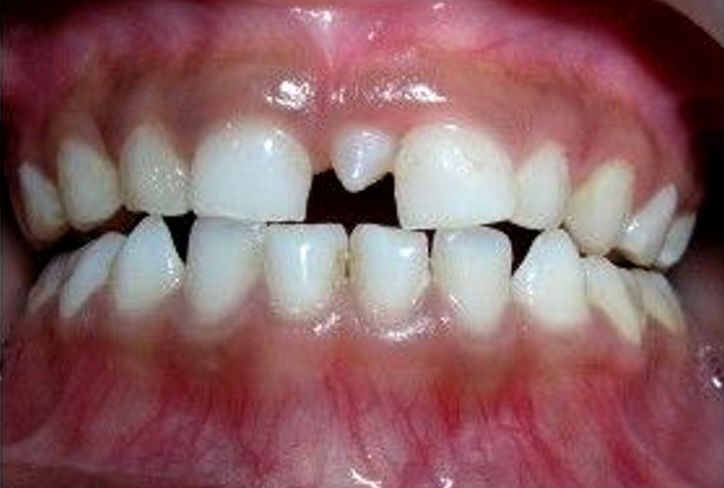

Hyperdontia: the presence of extra (supernumerary) teeth.

Below are examples of mild cases, and examples of extreme cases.

MILD CASES

Hyperdontia is the condition of having supernumerary teeth, or teeth that appear in addition to the regular number of teeth. They can appear in any area of the dental arch and can affect any dental organ.

There is evidence of hereditary factors along with some evidence of environmental factors leading to this condition. While a single excess tooth is relatively common, multiple hyperdontia is rare in people with no other associated diseases or syndromes. Many supernumerary teeth never erupt, but they may delay eruption of nearby teeth or cause other dental or orthodontic problems. Molar-type extra teeth are the rarest form. Dental x-rays are often used to diagnose hyperdontia.

The most common supernumerary tooth is a mesiodens, which is a malformed, peg-like tooth that occurs between the maxillary central incisors.